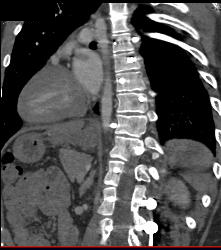

Diagnosis

Bakers Cyst